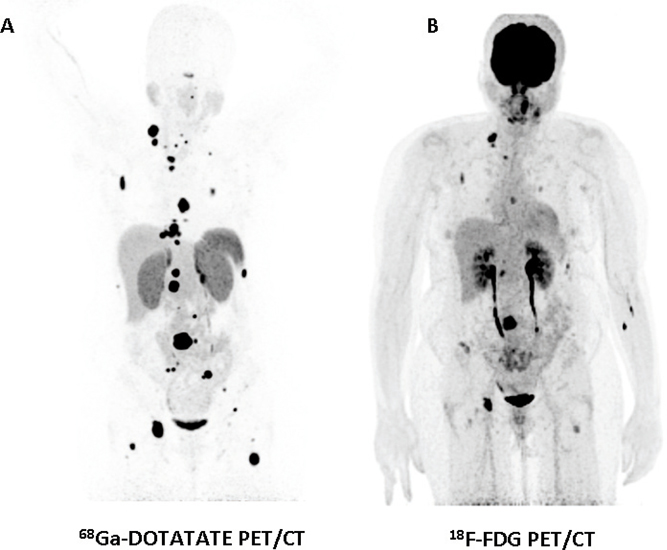

Functional imaging with PET using 18F-FDG is currently widely available. This is a versatile modality that can localize various tumors and aid the staging of neoplastic disease. 18F-FDG PET is a convenient and accessible modality for localizing PHEOs/PGLs that are negative with specific functional imaging modalities (particularly metastatic disease) (Figure 1) (22). In patients with succinate dehydrogenase beta (SDHB)-associated PHEO/PGL—which are more prone to malignant disease—18F-FDG PET has 97–100% sensitivity in localizing tumor lesions, whereas the sensitivity of 123I-MIBG is 65–80% and that of 18F-FDA PET is 70–88% (23).

Fig 1

Figure 1. Anterior maximum intensity projection images of 68Ga-DOTATATE (A) and 18F-FDG (B) PET/CT of a 48-year-old female patient with metastatic PGL; note more foci of uptake with 68Ga-DOTATATE compared to 18F-FDG. (Images courtesy of Karel Pacak, MD, PhD, DSc, Section on Medical Neuroendocrinology, NICHD, NIH, Bethesda, MD, USA.)

The expression of somatostatin receptors (ST-R) is common in PHEOs and PGLs (they mainly express type 2—mostly-, 3 and 5 ST-Rs (24); however, there are discrepancies in the literature and conflicting results have been presented). Octreotide is an octapeptidic somatostatin analog that is chelated with diethylenetriaminepentaacetate (DTPA) and labeled with indium-111 (111I-Pentetreotide) for ST-R scintigraphy (SRS). Although its splenic and renal accumulation is intense, it is nevertheless useful for localizing malignant/metastatic PHEOs/PGLs with a sensitivity approaching 90%. ST-R-based imaging may be less specific than 18F-DOPA PET imaging in the evaluation of PHEOs/PGLS (21). Furthermore, false positives may be expected in metastatic lymph nodes, meningiomas, and inflammation foci (21). Recently, novel 68 Gallium (68Ga)-DOTA-labeled somatostatin analogs (68Ga-DOTATATE, 68Ga-DOTANOC, and 68Ga-DOTATOC) have been introduced to clinical PET/CT use; they are reported to have higher sensitivity for detecting neuroendocrine tumors compared to “classic” SRS (25) (Figure 1). 68Ga-DOTATATE PET/CT was better than 18F-DOPA, 18F-FDA PET/CT, CT/MRI, and especially 18F-FDG PET/CT in imaging patients (n = 22) with sporadic metastatic PHEO/PGL (26), or head and neck PGLs (sensitivity reported at 93% in a series of 30 patients) (20).